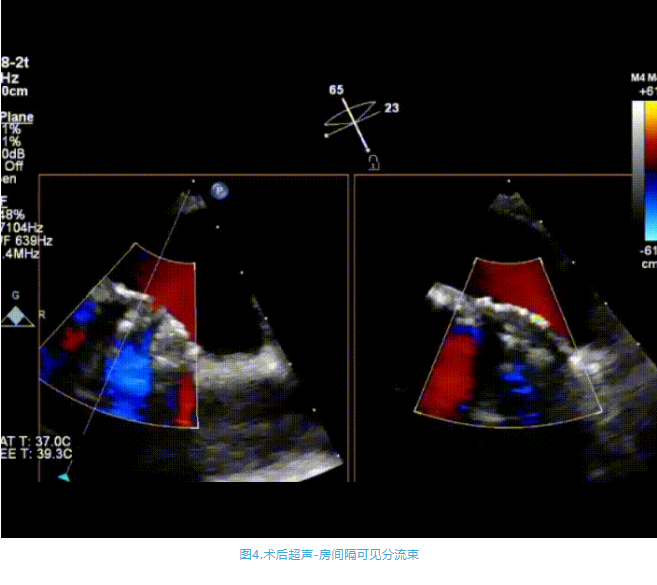

術(shù)中首先在局麻下穿刺股動(dòng)脈、股靜脈,完成心導(dǎo)管檢查評(píng)估后轉(zhuǎn)為全麻,在食道超聲引導(dǎo)下穿刺房間隔,穿刺成功后將加硬導(dǎo)絲送入左上肺靜脈建立軌道,根據(jù)患者病情行球囊預(yù)擴(kuò)張后植入6mm孔徑房間隔造孔支架,經(jīng)透視及食道超聲評(píng)估支架左右盤展開良好,夾持于房間隔兩側(cè),固定穩(wěn)定、位置良好,食道彩超顯示房水平右向左為主分流,分流孔直徑符合預(yù)期大小,心導(dǎo)管檢查評(píng)估達(dá)到預(yù)期效果,釋放造孔支架。術(shù)后12h患者下床活動(dòng),恢復(fù)順利,擬于近日完善術(shù)后評(píng)估后出院。

心房分流術(shù)是通過器械制造穩(wěn)定可控的心房間分流,適應(yīng)證包括藥物治療效果不佳的左心衰或肺動(dòng)脈高壓右心衰。本例患者為肺動(dòng)脈高壓右心衰,術(shù)中成功放置MicroFlux®造孔支架在房間隔理想位置上,創(chuàng)造穩(wěn)定可控的心房間分流(此例患者以右向左分流為主),在不顯著增加左心負(fù)擔(dān)的情況下,有效降低患者右心房壓力、緩解體循環(huán)淤血,增加左心輸出量,改善患者癥狀、活動(dòng)耐力和生存質(zhì)量。同時(shí),國(guó)內(nèi)外也已經(jīng)開展多項(xiàng)房間隔造孔支架在射血分?jǐn)?shù)保留、射血分?jǐn)?shù)中間值和射血分?jǐn)?shù)降低的左心衰患者中的臨床研究,結(jié)果顯示對(duì)于經(jīng)過充分的規(guī)范化藥物治療后仍控制不佳的患者,心房分流術(shù)可改善患者的癥狀及生存質(zhì)量?! ?/p>